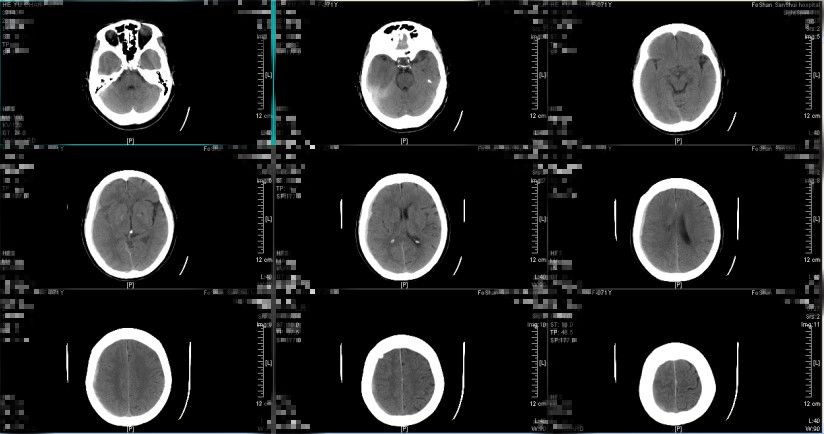

患者于2019年1月3日早上8点左右出现意识障碍,神志模糊,GCS评分10分,考虑硬膜下血肿继续增多、颅压高引起,予20%甘露醇250ml 快速静滴并同时送至CT室复查头颅CT提示(图7、图8):亚急性硬膜下血肿继续较前增多,最大厚度约2cm,中线向左偏移大于1cm,环池受压,有明确的手术指征。经脱水药物处理后,患者神志转清,GCS评分上升到14分,再次与患者及其家属讲解病情及治疗方案,选择予微创手术治疗方案。遂于当天早上9点左右行右额部微创针穿刺亚急性硬膜下血肿引流术,术中予生理盐水反复置换冲洗,术后行定时开放、夹闭引流,行阶梯性减压,利用脑复张促进血肿引流。

图7.(2019-01-03 08:34:45)

图8

留置头部微创针引流管引流1天,引流量约200ml,患者神志清,头痛等症状减轻,复查头颅CT提示亚急性硬膜下血肿大部分消除,最大厚度约0.2cm,中线大致居中,环池清晰,手术效果明显,予拔除微创针引流管,继续与立普妥药物治疗。

图9. 术后24小时复查头颅CT提示:亚急性硬膜下血肿大部分消除,中线大致居中,环池清晰。(2019-01-04 10:01:05)

图10. 术后9天复查头颅CT提示亚急性硬膜下血肿基本吸收。(2019-01-12 16:17:43)

经治疗后,患者神志清,头痛等症状缓解,无遗留神经系统缺损体征,复查头颅CT提示亚急性硬膜下血肿基本吸收,病情稳定,于2019年1月14日出院。

2019年1月29日门诊复查头颅CT(图11、图12)如下:提示亚急性硬膜下血肿已吸收,未见新发血肿形成。